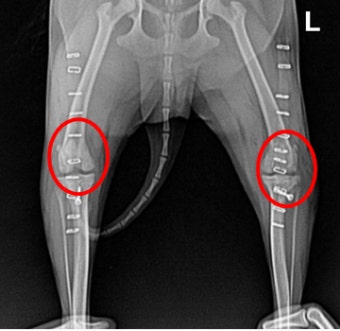

5. 단계별로 알아보는 슬개골 탈구 등급

| 1등급 | 슬개골이 간헐적으로 빠지지만 바로 제자리로 돌아감 |

| 2등급 | 빠지면 손으로 눌러야 돌아옴 |

| 3등급 | 대부분 탈구 상태이며, 가끔만 정상 위치 |

| 4등급 | 항상 탈구 상태, 무릎 관절이 고정되지 않음 |

8. 슬개골 탈구 치료 방법

1~2등급의 경우에는 비수술적 요법(물리치료, 체중조절)도 가능합니다.

3~4등급이라면 대부분 수술을 권장해요. 관절을 제자리에 고정하고 연골 손상을 줄이기 위해서죠.